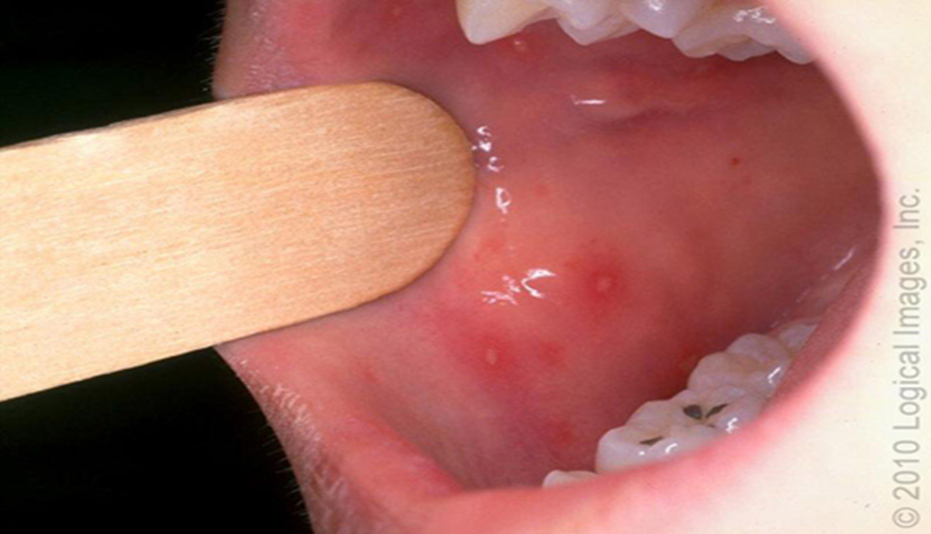

დაავადების კარდინალური ნიშანია ორალური ენანთემა (სურათი 1 ა-ბ) და ეგზანთემა (სურათი 2) , თუმცა შესაძლოა იყოს ენანთემა ეგზანთემის გარეშე, ან ეგზანთემა ენანთემის გარეშე.

სურათი 1 -ა

ორალური ენანთემა – ორალური დაზიანება შეიძლება მოიცავდეს მთელ პირის ღრუს, თუმცა უმეტესად ზიანდება სასის რკალები, ენა და ლოყის ლორწოვანი (სურათი 1 ა-ბ). შედარებით ნაკლებად ერთვება პროცესში გინგივოლაბიალური ღარი, მაგარი და რბილი სასა. ზოგჯერ მოიცავს ნაქს, ტუჩებსა და ტონზილებს.

ენანთემა იწყება ერითემატოზული მაკულებით, რომელიც პროგრესირდება ვეზიკულებად, ირგვლივ ერითემული უბნებით (სურათი 1-ბ). ვეზიკულების დიამეტრი ცვალებადობს 1მმ-დან 5 მმ-მდე. შეიძლება იყოს უფრო დიდი ზომის. ვეზიკულები სწრაფად სკდებიან და წარმოქმნიან მონაცრისფრო – მოყვითალო ზედაპირულ წყლულებს, ერითემატოზული რგოლით (სურათი 1-ა). წყლულების დიამეტრი ჩვეულებრივ 1მმ-დან 10 მმ-მდე მერყეობს, იშვიათად აღწერილია 20 მმ ზომის წყლულოვანი ელემენტებიც.

ხფპდ დიაგნოზი ჩვეულებრივ ისმება კლინიკურად ორალური ენანთემის ტიპიური ლოკალიზაციის და მიმდინარეობის (სურათი 1 ა-ბ) და ეგზანთემის (სურათი 2) მიხედვით. დიაგნოსტირება შესაძლოა გართულდეს, თუ დაავადება მხოლოდ ენანთემით ან ეგზანთემით მიმდინარეობს. თუმცა უმრავლეს შემთხვევაში დაავადება მიმდინარეობს ორივე სახის გამონაყრით და მხოლოდ 10-15 % ში გვხვდება მხოლოდ ენანთემა ან ეგზანთემა.